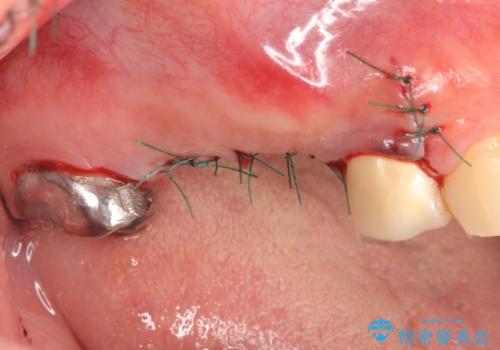

右上の567ブリッジを外したところ、右上5は歯根破折により保存不可能だったため、右上56部にインプラントを埋入し欠損補綴を行いました。

また右上5部に関しては抜歯時に歯槽堤保存術(抜歯窩に人工骨の填入を行う手術)を行い、骨の欠損を最小限に止めています。